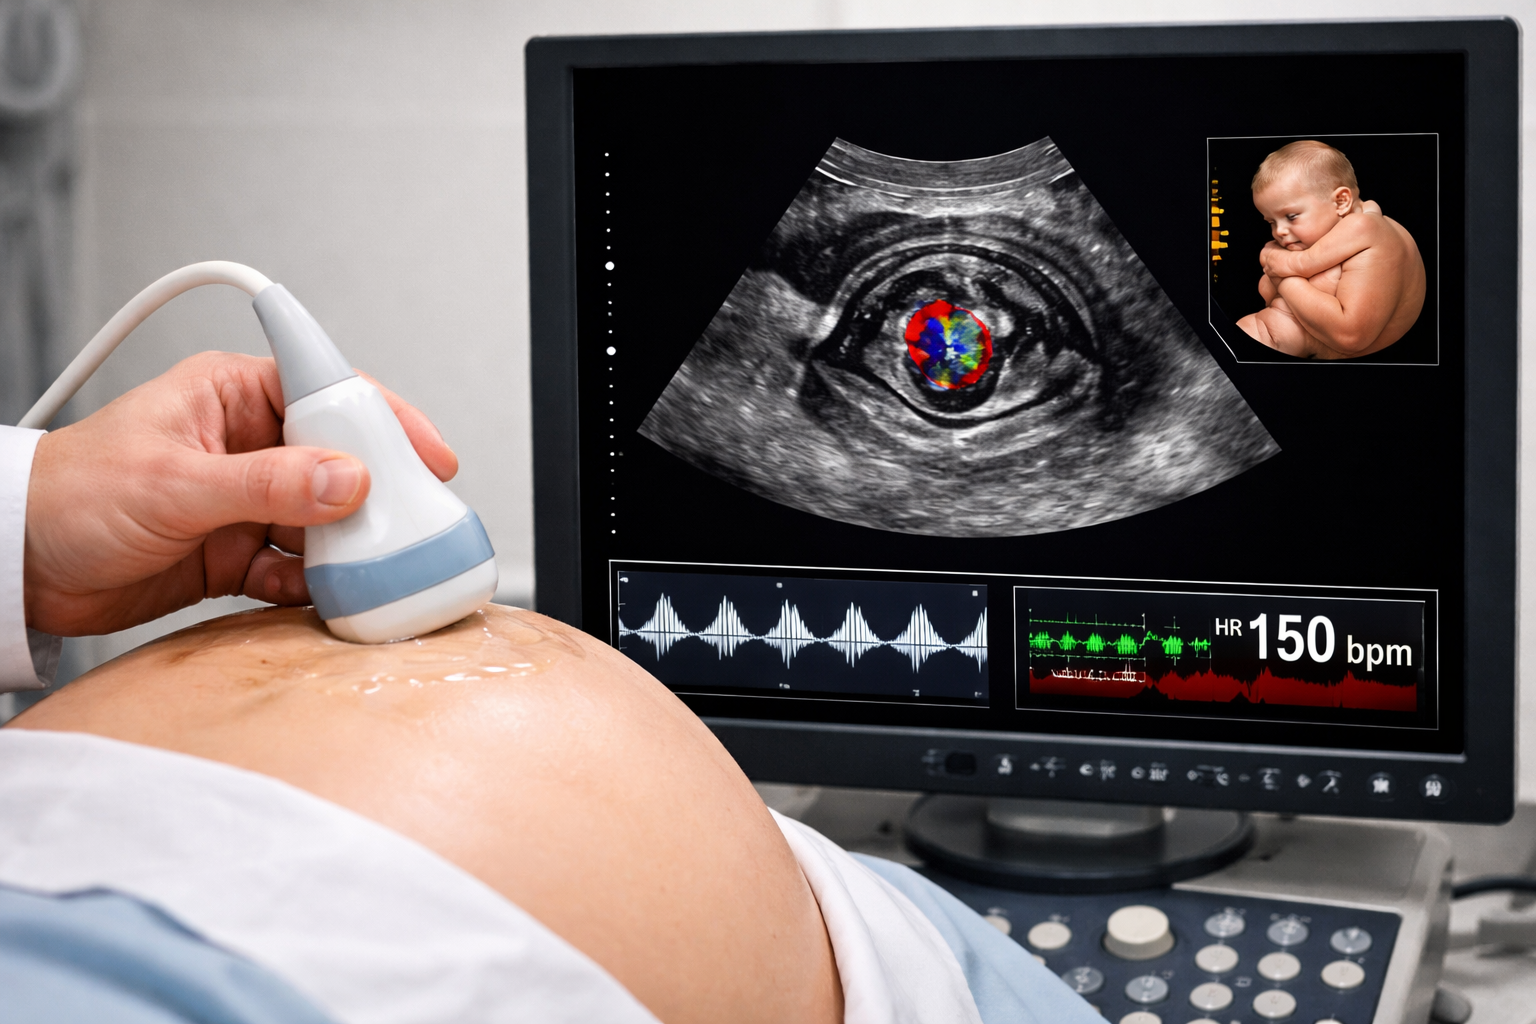

Il centro cardiologico infantile del Dott. Rosati mette a tua disposizione medici cardiologi di comprovata esperienza in cardiologia pediatrica. Gli specialisti operano nello studio di Brindisi con l'ausilio di apparecchiature all'avanguardia, ricevendo i piccoli pazienti in un ambiente accogliente e rassicurante. L'obiettivo è garantire il miglior trattamento possibile, grazie a un approccio multi disciplinare che consente di prevenire, diagnosticare e curare le patologie cardiologiche pediatriche in modo tempestivo ed efficace.In particolare, il centro cardiologico è specializzato nelle cardiopatie dell'età pediatrica, come quelle congenite, quelle acquisite con esordio in età pediatrica e nell'adolescenza, e le cardiopatie fetali.

Alcuni video di patologie cardiache

Nel sito del centro cardiologico infantile del Dott. Enrico Rosati troverai alcuni video riguardanti alcuni casi di cardiopatie fetali diagnosticati presso lo studio medico di Brindisi. I video riguardano l'atresia polmonare, l'anomalia di Ebstein, la coartazione aortica, il TGA fetale e il canale atrioventricolare. Non esitare a contattare la segreteria per richiedere informazioni o fissare un appuntamento per il tuo bambino.